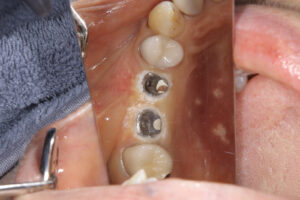

インプラント埋入直後

インプラント周囲炎

インプラント周囲の臭い

インプラント周囲炎を治す